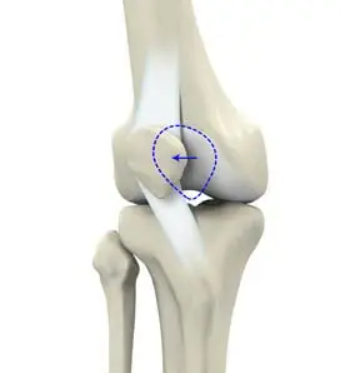

髕骨脫位(patelladislocation)是指髕骨由于多種因素脫離正常的運動軌跡向外側(cè)脫位,是最常見的急性膝關(guān)節(jié)損傷之一,占急性膝關(guān)節(jié)損傷的3%,常見于兒童和青少年。在過去的幾十年,由于參加體育運動的人數(shù)越來越多,導(dǎo)致髕骨脫位的發(fā)病率越來越高,每100,000人中就有5.8~77.8個人患有髕骨脫位,且女性較男性的發(fā)病率更高。髕骨脫位的病因眾多,通常與骨性異常或軟組織病變有關(guān)。骨性異常1.高位髕骨(patellaalta):指由于髕韌帶長度過長(>52mm)導(dǎo)致髕骨在矢狀面的垂直高度增加,是一種先天性的異常。高位髕骨是復(fù)發(fā)性髕骨脫位的高危因素,在屈膝早期階段,髕骨進入股骨滑車溝延遲,與股骨滑車的接觸面減少,骨性穩(wěn)定作用減弱,容易發(fā)生脫位。Caton指數(shù)>1.2可協(xié)助診斷。2.低位髕骨(patellainfera):指髕骨在矢狀面的垂直高度降低,大多數(shù)為獲得性,可以由外傷導(dǎo)致,也與不恰當?shù)闹委熡嘘P(guān)。根據(jù)病因,低位髕骨可分為:先天性、創(chuàng)傷性、制動性、麻痹性和醫(yī)源性。Caton?0.6,Insall<0.8可明確診斷。3.滑車發(fā)育不良:指患者的股骨滑車沒有發(fā)育成正常的凹面的解剖形狀,而是成為平坦的甚至是凸起的形狀?;颊叩墓晒腔嚋系赘叨犬惓#诨嚱诵纬晒切酝蛊?,突出于股骨干前方皮質(zhì),導(dǎo)致髕骨不得不越過滑車近端的骨性凸起才能進入滑車,從而導(dǎo)致髕骨脫位。20世紀90年代,H.Dejour首次提出采用膝關(guān)節(jié)純側(cè)位X線片評估滑車發(fā)育不良的方法,將滑車發(fā)育不良分成4型。A型:純側(cè)位片僅有交叉征,軸位片可見滑車較正常平坦。B型:純側(cè)位片可見交叉征和突起征,軸位片可見滑車外側(cè)面凸起或平坦。C型:純側(cè)位片同時可見交叉征和雙線征,但沒有突起征。軸位片可見滑車外側(cè)面凸起,內(nèi)側(cè)面發(fā)育不良。D型:純側(cè)位片同時可見交叉征、雙線征和突起征,軸位片可見滑車外側(cè)面突起,內(nèi)側(cè)滑車發(fā)育不良,甚至形成“懸崖征”(cliffsign)。4.脛骨結(jié)節(jié)過度外偏:目前脛骨結(jié)節(jié)-股骨滑車間距(tibialtubercle-trochleargroovedistance,TT-TG)通常在膝關(guān)節(jié)伸直位進行CT掃描測量,第一個掃描層面通常為通過股骨滑車關(guān)節(jié)軟骨的首個掃描平面,第二個層面通過脛骨結(jié)節(jié)的近端。TT-TG的正常參考值為<12mm,TT-TG>20mm的患者,可在MPFL重建術(shù)的基礎(chǔ)上聯(lián)合脛骨結(jié)節(jié)截骨術(shù)。軟組織病變1.多韌帶松弛癥:多發(fā)關(guān)節(jié)松弛癥(generalizedlaxity)和膝關(guān)節(jié)局部松弛癥(localizedjointlaxity)是髕股關(guān)節(jié)不穩(wěn)定的常見易患因素之一。Beighton診斷標準:滿分9分,成年人≥4分,兒童?6分即可診斷多發(fā)關(guān)節(jié)松弛癥。2.髕內(nèi)側(cè)穩(wěn)定結(jié)構(gòu)損傷:內(nèi)側(cè)髕骨股骨韌帶(medialpatellofemoralligament,MPFL)是限制髕骨外移的一級穩(wěn)定結(jié)構(gòu),是髕骨穩(wěn)定的最重要的軟組織穩(wěn)定結(jié)構(gòu)。MPFL斷裂后不僅會導(dǎo)致髕骨外移的顯著增加,同時還將增大股骨滑車外側(cè)面的壓力,導(dǎo)致膝前痛、骨性關(guān)節(jié)炎等疾病。根據(jù)遺傳病因?qū)W,髕骨脫位可分為復(fù)發(fā)性髕骨脫位、習(xí)慣性髕骨脫位和先天性髕骨脫位。復(fù)發(fā)性髕骨脫位:復(fù)發(fā)性髕骨脫位是由于急性髕骨脫位發(fā)展而來,常常伴隨內(nèi)側(cè)髕骨股骨韌帶損傷,并可能伴有髕骨內(nèi)側(cè)關(guān)節(jié)軟骨或股骨外髁骨軟骨骨折,通??勺孕袕?fù)位。多數(shù)患者自訴在受傷時有“髕骨錯位感”,臨床檢查可發(fā)現(xiàn)膝關(guān)節(jié)內(nèi)側(cè)支持帶區(qū)域壓痛、膝關(guān)節(jié)內(nèi)側(cè)血腫以及髕骨外推恐懼試驗陽性。習(xí)慣性髕骨脫位:習(xí)慣性髕骨脫位又稱隨意性髕骨脫位。表現(xiàn)為每次屈膝時均發(fā)生髕骨脫位,完全伸膝時復(fù)位,患者通常沒有疼痛主訴。其發(fā)病機制是由于股四頭肌的短縮,因此若手法強行限制髕骨脫位,膝關(guān)節(jié)的屈曲會受限。在習(xí)慣性髕骨脫位的患者中,常合并膝外翻(valgus)、股骨滑車發(fā)育不良(trochleardysplasia)、伸膝裝置短縮、脛骨結(jié)節(jié)外偏(tibialtuberclelateralization)、股骨和脛骨扭轉(zhuǎn)畸形(femoralandtibialtorsionaldeformity)等。固定性髕骨脫位:固定性髕骨脫位包括先天性髕骨脫位以及由外傷導(dǎo)致的急性髕骨脫位發(fā)展而來。前者是出生時即出現(xiàn)的髕骨脫位(通常在10歲以前發(fā)現(xiàn));后者是因外傷導(dǎo)致髕內(nèi)側(cè)穩(wěn)定結(jié)構(gòu)完全失去穩(wěn)定功能。固定性髕骨脫位的患者,無論膝關(guān)節(jié)是伸直還是屈曲,髕骨始終處于脫位狀態(tài)且不能復(fù)位。與習(xí)慣性髕骨脫位相比,復(fù)發(fā)性髕骨脫位的患者往往有明顯的外傷史,習(xí)慣性髕骨脫位的患者可能伴隨先天性的骨性異常以及軟組織病變。復(fù)發(fā)性髕骨脫位可通過保守治療恢復(fù)髕骨穩(wěn)定性,但二次損傷可能導(dǎo)致髕骨再次脫位,每次均可通過手法復(fù)位;而習(xí)慣性髕骨脫位可在每次屈膝時出現(xiàn),僅在完全伸膝時可復(fù)位,強行手法復(fù)位可能會導(dǎo)致膝關(guān)節(jié)活動受限。因此在臨床診斷時,需詳細詢問病人的病史,并結(jié)合查體謹慎辨別兩種髕骨脫位。髕骨脫位的治療方案可分為保守治療和手術(shù)治療。對于初發(fā)的急性髕骨脫位,可采取保守治療?;颊咄ㄟ^3周的鉸鏈式伸直位支具固定,配合理療和藥物治療可緩解腫脹和疼痛,3周后可在專業(yè)康復(fù)師的指導(dǎo)下進行康復(fù)訓(xùn)練:ROM訓(xùn)練恢復(fù)關(guān)節(jié)活動度、VMO強化訓(xùn)練和核心肌群訓(xùn)練增強髕骨穩(wěn)定性以及髂脛束拉伸訓(xùn)練減少髕骨外側(cè)牽拉力。6周后門診復(fù)查,若保守治療無效,無法維持復(fù)位或反復(fù)脫位者則建議手術(shù)治療。手術(shù)治療要根據(jù)患者存在的主要病理因素設(shè)計手術(shù)方案,即使是同一種脫位類型,在不同患者可能會接受不同的手術(shù)方案。手術(shù)方案包括兩大類。一是近端力線矯正術(shù),二是遠端力線矯正術(shù)。近端力線矯正術(shù)包括:股骨遠端截骨術(shù)、滑車成形術(shù)、外側(cè)支持帶松解或延長術(shù)以及MPFL重建術(shù)等;遠端力線矯正術(shù)包括脛骨結(jié)節(jié)截骨術(shù)、髕腱外側(cè)半內(nèi)移術(shù)、脛骨近端截骨術(shù)等。多數(shù)髕骨脫位患者需要接受MPFL重建術(shù)。可選擇不同的移植物代替原本的MPFL,自體移植物包括自體半腱肌腱、股薄肌腱、內(nèi)收肌腱、股四頭肌腱、髕韌帶、髂脛束及闊筋膜等,異體移植物包括異體骨-髕腱復(fù)合體、異體脛前肌腱或半腱肌腱等,或人工韌帶。臨床多選用自體半腱肌腱作為移植物。髕骨脫位是臨床青少年人群較為常見的膝關(guān)節(jié)疾病,明確其分型對于治療方案的選擇和治療效果至關(guān)重要。在手術(shù)治療前要認真、個體化地分析導(dǎo)致患者髕骨脫位的病理因素。手術(shù)治療要圍繞引起患者髕骨脫位的主要病理因素設(shè)計手術(shù)方案,同一類型的髕骨脫位也可能通過不同術(shù)式解決。